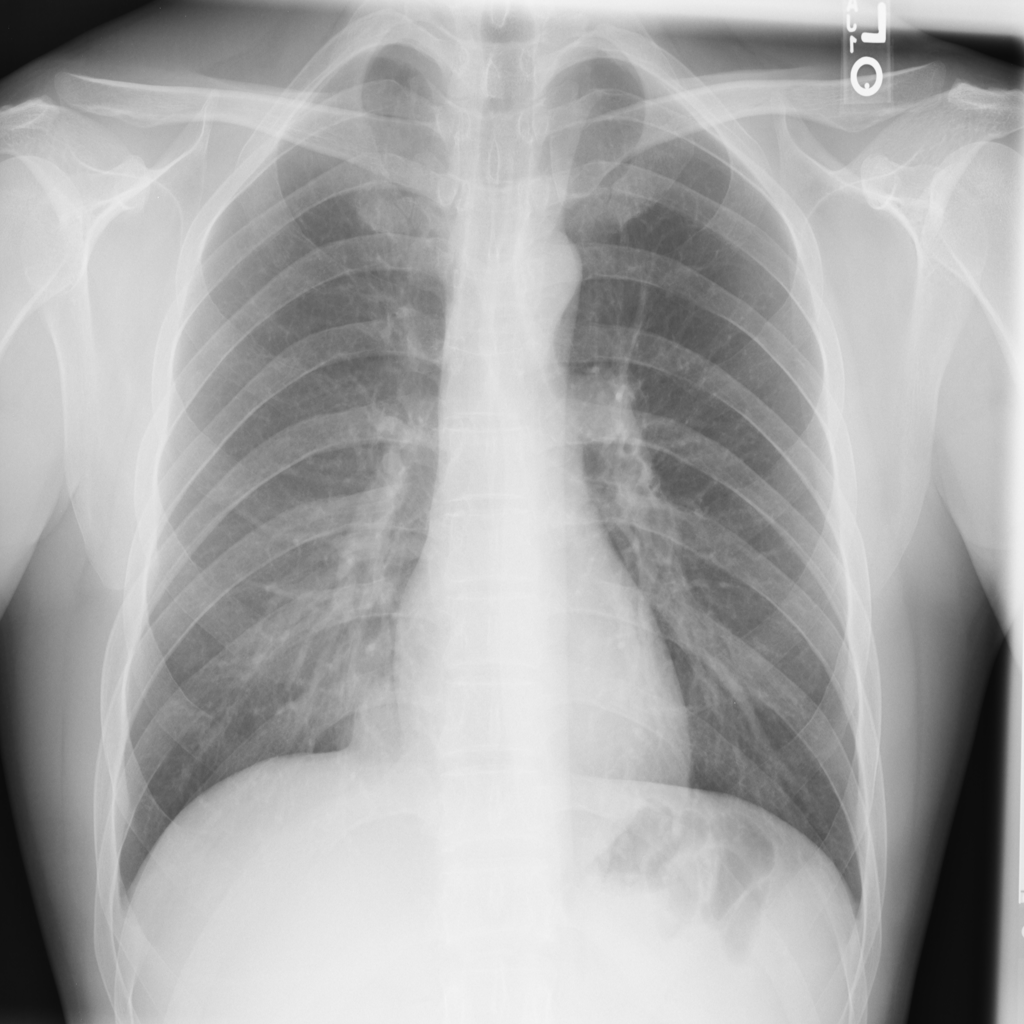

NIH Chest X-Ray dataset (Wang et al., 2017) is a large-scale medical imaging dataset comprised of 112120 X-ray images from 30805 patients. Figure 2 shows a few sample X-Ray images from the dataset. The X-ray images come labeled with up to 14 diseases and “No finding” by natural language processing (NLP) models based on the original radiological reports of each X-ray. We only select samples with “No Findings” and disease “Effusion” for the scope of our experiments. We use “Effusion” as the target label, and “Patient gender” as the sensitive attribute. After removing entries filled with N/A and abnormal values, we have a dataset with 73669 samples, and 13316 (18.1%) are labeled “Effusion”. In addition, we resized each image into size (256 * 256 * 3) with 3 channels both for computational reasons and the requirement for using pre-trained models during the training process (to be discussed in Section 6). Images are also normalized using the required mean and standard deviation based on the pre-trained model used in the experiments (Sandler et al., 2019). Detailed statistics of NIH Chest X-Ray are in Table 4.

EffusionEffusion

Total 1 0 Total

gendergender

1 7434 (10.1%) 33916 (46.0%) 41350 (56.1%56.1\%)

0 5882 (8.0%) 26437 (35.9%) 32319 (43.9%)

Total 13316 (18.1%18.1\%) 60353 (81.9%81.9\%) 73669 (100.0%)

Table 4. Statistics for NIH-Chest X-Ray dataset. EffusionEffusion is used as target label and gendergender as sensitive attribute.

Refer to caption

Figure 2. Four sample Chest X-ray images from NIH Chest X-Ray dataset.